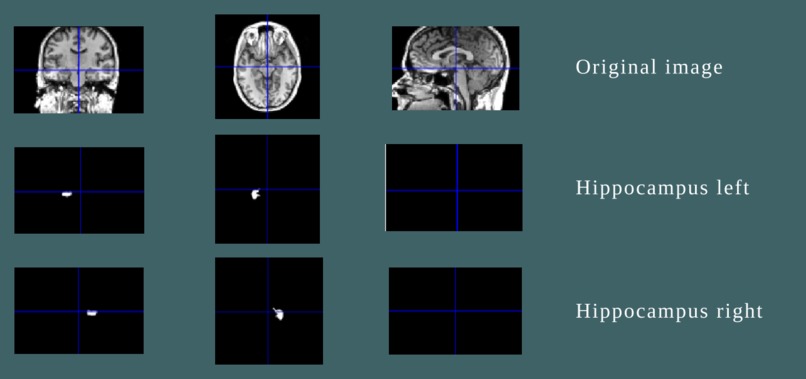

Segmentation- Our first step

Segmentation is the extraction of the required region of interest(RoI) from the MRI scans. For segmentation of the Brain MRI for the hippocampal region, we have used a deep 3-D convolutional network. From the segmented images, the volume of the hippocampal region can be calculated. This can give the doctors better and accurate calculations.

Segmentation of the hippocampus area and quantification of the hippocampal region are done with the 3D-CONV net using Brain MRI. The classification of NC and MCI is done first using the hippocampus volumes. Then these MCI subjects are further classified as AD and MCI using the CSF biomarkers. The classification of different stages of AD is done using two different biomarkers. This method of using different features to classify separately is the innovation here. Using this innovative approach, we were able to get much more accurate results.